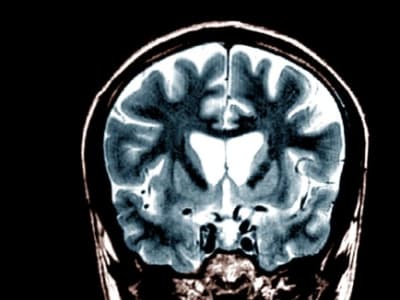

Shanghai , China - Mikroglia adalah sel imun spesial di otak yang berfungsi penting untuk menjaga kesehatan otak dengan membersihkan zat berbahaya dan membantu melindungi neuron. Kerusakan mikroglia dapat menyebabkan berbagai penyakit serius, termasuk kondisi langka dan penyakit neurodegeneratif seperti Alzheimer dan Parkinson.

Beberapa penelitian terbaru menunjukkan bahwa penggantian mikroglia yang rusak oleh mikroglia baru yang sehat dapat membantu mengobati penyakit otak tertentu. Namun, proses penggantian ini sangat kompleks karena mikroglia biasanya memperbaharui diri dalam otak dan tidak mudah digantikan oleh sel dari luar.